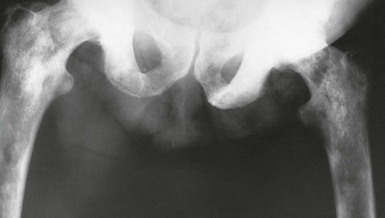

If a patient has skeletal pain, X-rays and radionuclide bone scans are indicated. On X-ray, prostatic bony metastases are typically sclerotic or osteoblastic (i.e. dense, appearing white on X-rays) rather than lytic (as in most other bony secondaries), giving the characteristic patchy ‘cotton-wool’ appearance shown in Figure 35.6. Some lesions, however, are radiolucent. An isotope bone scan can reveal metastases even when a plain X-ray is normal.